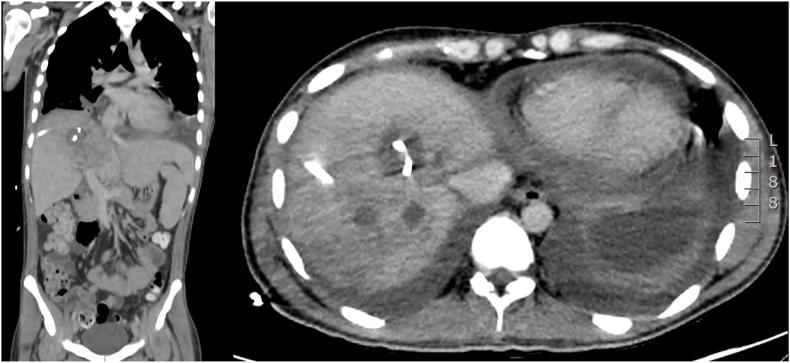

We present the unique case of a patient who was diagnosed with an actinomycotic liver abscess after coronavirus disease 2019 (COVID-19) without the presence of any chronic disease or mucosal injury.

According to the results of the computer tomography (CT scan) and the liver biopsy, the patient was treated with antibiotics and ultrasound-guided drainage.

我们呈现了一例独特病例,该患者在感染2019冠状病毒病(COVID-19)后被诊断出患有放线菌性肝脓肿,且不存在任何慢性疾病或黏膜损伤。

根据计算机断层扫描(CT扫描)结果和肝活检结果,该患者接受了抗生素治疗及超声引导下引流。